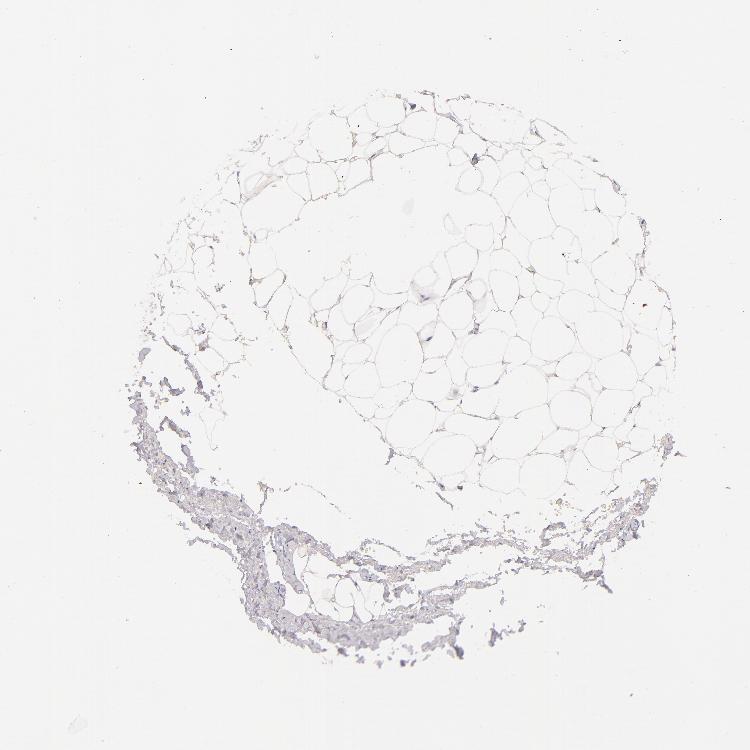

TISSUE PRIMARY DATA SOFT TISSUE Show tissue menu

SOFT TISSUE 1 - Antibody stainingi

Antibody staining in the annotated cell types in the current human tissue is reported as not detected, low, medium, or high, based on conventional immunohistochemistry profiling in selected tissues. This score is based on the combination of the staining intensity and fraction of stained cells.

Each image is clickable and will lead to virtual microscopy that enables deeper exploration of all samples and also displays staining intensity scores, fraction scores and subcellular localization as well as patient and tissue information for each sample.

Antibody HPA028275Antibody CAB002305

Chondrocytes -Not detected

Fibroblasts Not detectedNot detected

Peripheral nerve Not detectedNot detected

SOFT TISSUE 2 - Antibody stainingi

Chondrocytes Not detected-

Peripheral nerve -Not detected